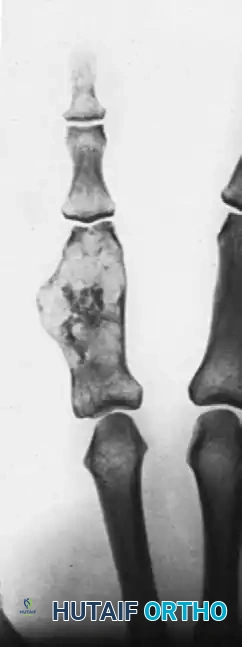

Radiographically, benign enchondromas present as well-circumscribed, central lytic lesions with stippled calcifications. Malignant transformation is heralded by endosteal scalloping (exceeding two-thirds of the cortical thickness), cortical breakthrough, soft-tissue extension, and a "fluffy radiopacity."

Above: Posteroanterior, lateral, and oblique radiographic views demonstrating a chondrosarcoma arising in a pre-existing enchondroma of 40 years’ duration. Note the greatly expanded proximal phalanx with clearly visible fluffy radiopacity and cortical destruction.